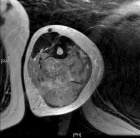

16 yo female w/ 6 mo h/o of painful mass in L arm with increasing size. Complains of dysthesias in her 4th and 5th digits. Denies constitutional symptoms. Previous bx reported as fatty tissue.

PE: Significant palpable, painful mass in posterior LUE. No erythema or overlying skin changes. Full ROM at shoulder and elbow. Decreased sensation to 4th webspace and 5th digit. 2+R/U pulses. No LAN.